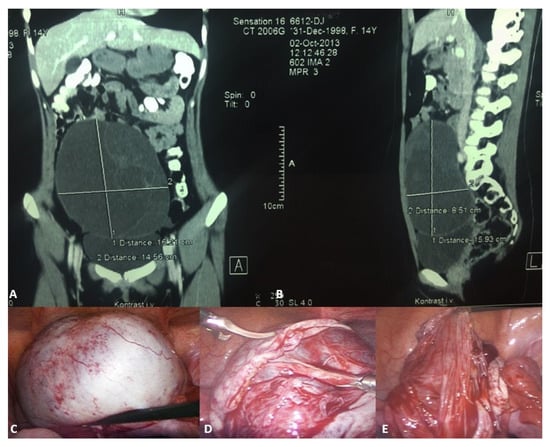

In the phase of adolescence, the possibility of obstructive genital anomalies, ovarian tumors, tubal conditions, uterine masses, and urologic and gastrointestinal conditions should be considered in the differential diagnosis. Ultrasound is the initial imaging modality in differentiating ovarian cysts from other possible conditions [2,47]. As for follicular cysts in adolescent girls, they usually disappear spontaneously within eight weeks. At this age, monophasic combination estrogen/progestin oral contraceptive pills (OCPs) containing ≥35 mcg ethinyl estradiol are commonly recommended, as they inhibit the ovarian-hypothalamic axis and can stop ovulation and the development of a new functional cyst [48,49]. Indications for laparoscopic cystectomy or aspiration are persistence for ≥3 months, size ≥ 6 cm (simple cysts measuring 6 to 12 cm may resolve spontaneously and can be monitored safely in certain patients), pelvic pain, or urinary frequency. Because of the high recurrence rate in the case of aspiration, laparoscopic cystectomy is usually preferred [50,51,52]. For corpus luteum cysts, observation for three months is also recommended for asymptomatic patients. Monophasic combination estrogen/progestin OCPs with ≥35 mcg ethinyl estradiol are also prescribed. Cystectomy alone is rarely warranted. Persistent or non-involuting ovarian cysts should be treated through cystectomy and ovarian tissue preservation (Figure 3) [49,53,54].

Figure 3.

A 14-year-old girl presented with intermittent abdominal pain, loss of appetite, and a palpable abdominal mass. (A) Multislice computed tomography revealed a giant right abdominal ovarian cyst measuring 16.2 × 14.6 cm; (B) The cystic mass filled the entire lower abdomen and was pressing on the surrounding structures; (C) Laparoscopic examination revealed a giant ovarian cyst; (D) The ovarian cortex was opened, 2 L of clear contents were aspirated; (E) A laparoscopic cystectomy with ovarian sparing was performed. A pathohistological examination revealed a simple ovarian cyst. Source: Archive of the Department of Pediatric Surgery, University Hospital of Split.